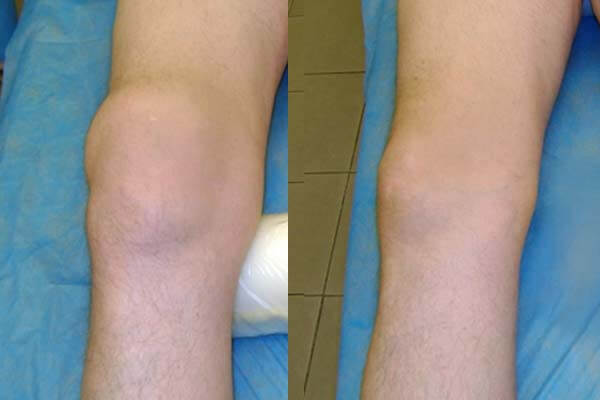

Foto rontgen sendi lutut sebelum dan sesudah mengonsumsi bubuk Invanil

Hasil pengobatan sendi lutut